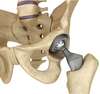

Cependant, si vos symptômes résistent au traitement médical bien conduit et entraîne une diminution de votre qualité de vie, le remplacement de votre articulation par une prothèse totale de hanche semble être la meilleure option.

Pour plus d’information sur la prothèse de hanche, veuillez cliquer sur l’onglet ci-dessous.